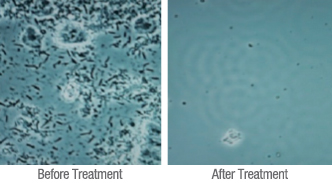

Gum Bleaching

De-Epithelialization and Soft Tissue Management